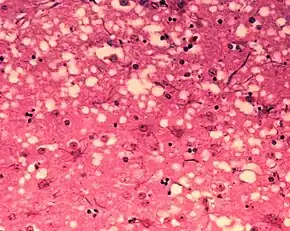

The agent is not destroyed even if the beef or material containing it is cooked or heat-treated.[15] Transmission can occur when healthy animals come in contact with tainted tissues from others with the disease. In the brain, the agent causes native cellular prion protein to deform into the misfolded state, which then goes on to deform further prion protein in an exponential cascade. This results in protein aggregates, which then form dense plaque fibers. Brain cells begin to die off in massive numbers, eventually leading to the microscopic appearance of "holes" in the brain, degeneration of physical and mental abilities, and ultimately death.

Diagnosis of BSE continues to be a practical problem. It has an incubation period of months to years, during which no signs are noticed, though the pathway of converting the normal brain prion protein (PrP) into the toxic, disease-related PrPSc form has started. At present, virtually no way is known to detect PrPSc reliably except by examining post mortem brain tissue using neuropathological and immunohistochemical methods. Accumulation of the abnormally folded PrPSc form of PrP is a characteristic of the disease, but it is present at very low levels in easily accessible body fluids such as blood or urine. Researchers have tried to develop methods to measure PrPSc, but no methods for use in materials such as blood have been accepted fully.

The traditional method of diagnosis relies on histopathological examination of the medulla oblongata of the brain, and other tissues, post mortem. Immunohistochemistry can be used to demonstrate prion protein accumulation.[24]